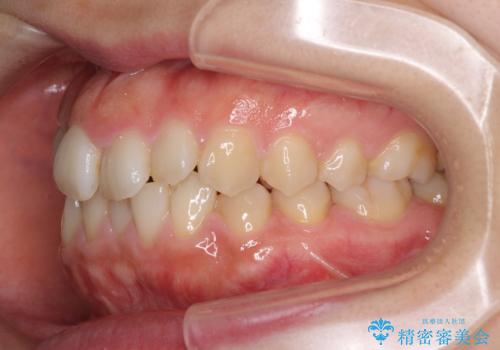

- 右上の八重歯と、左下八重歯を抜いてしまったことを気にして来院された患者様です。

下顎は既に犬歯を1本抜歯しているため、上顎右側第一小臼歯を抜歯し、ワイヤー装置にて歯列を整えることとしました。

変則的な抜歯となるため、正中と人中がずれる可能性がありましたが、仕上がりは上下正中を揃えることができました。